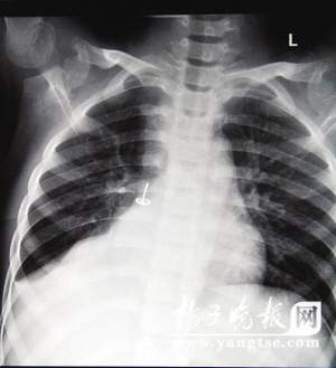

從片子上,圖釘在孩子右肺里“潛伏”得很深,卡在右下葉支氣管。南京市兒童醫(yī)院耳鼻喉科周艾醫(yī)生表示,由于圖釘堵住了孩子支氣管的通道,導(dǎo)致右肺葉不擴張,肺部已經(jīng)發(fā)生了實質(zhì)性的改變,用擴張來進行氧氣交換的肺泡都已經(jīng)“癟”下去了,所以孩子的肺部功能非常弱。從片子上看,孩子的右肺已經(jīng)嚴(yán)重“萎縮”,比左肺小了一大圈。